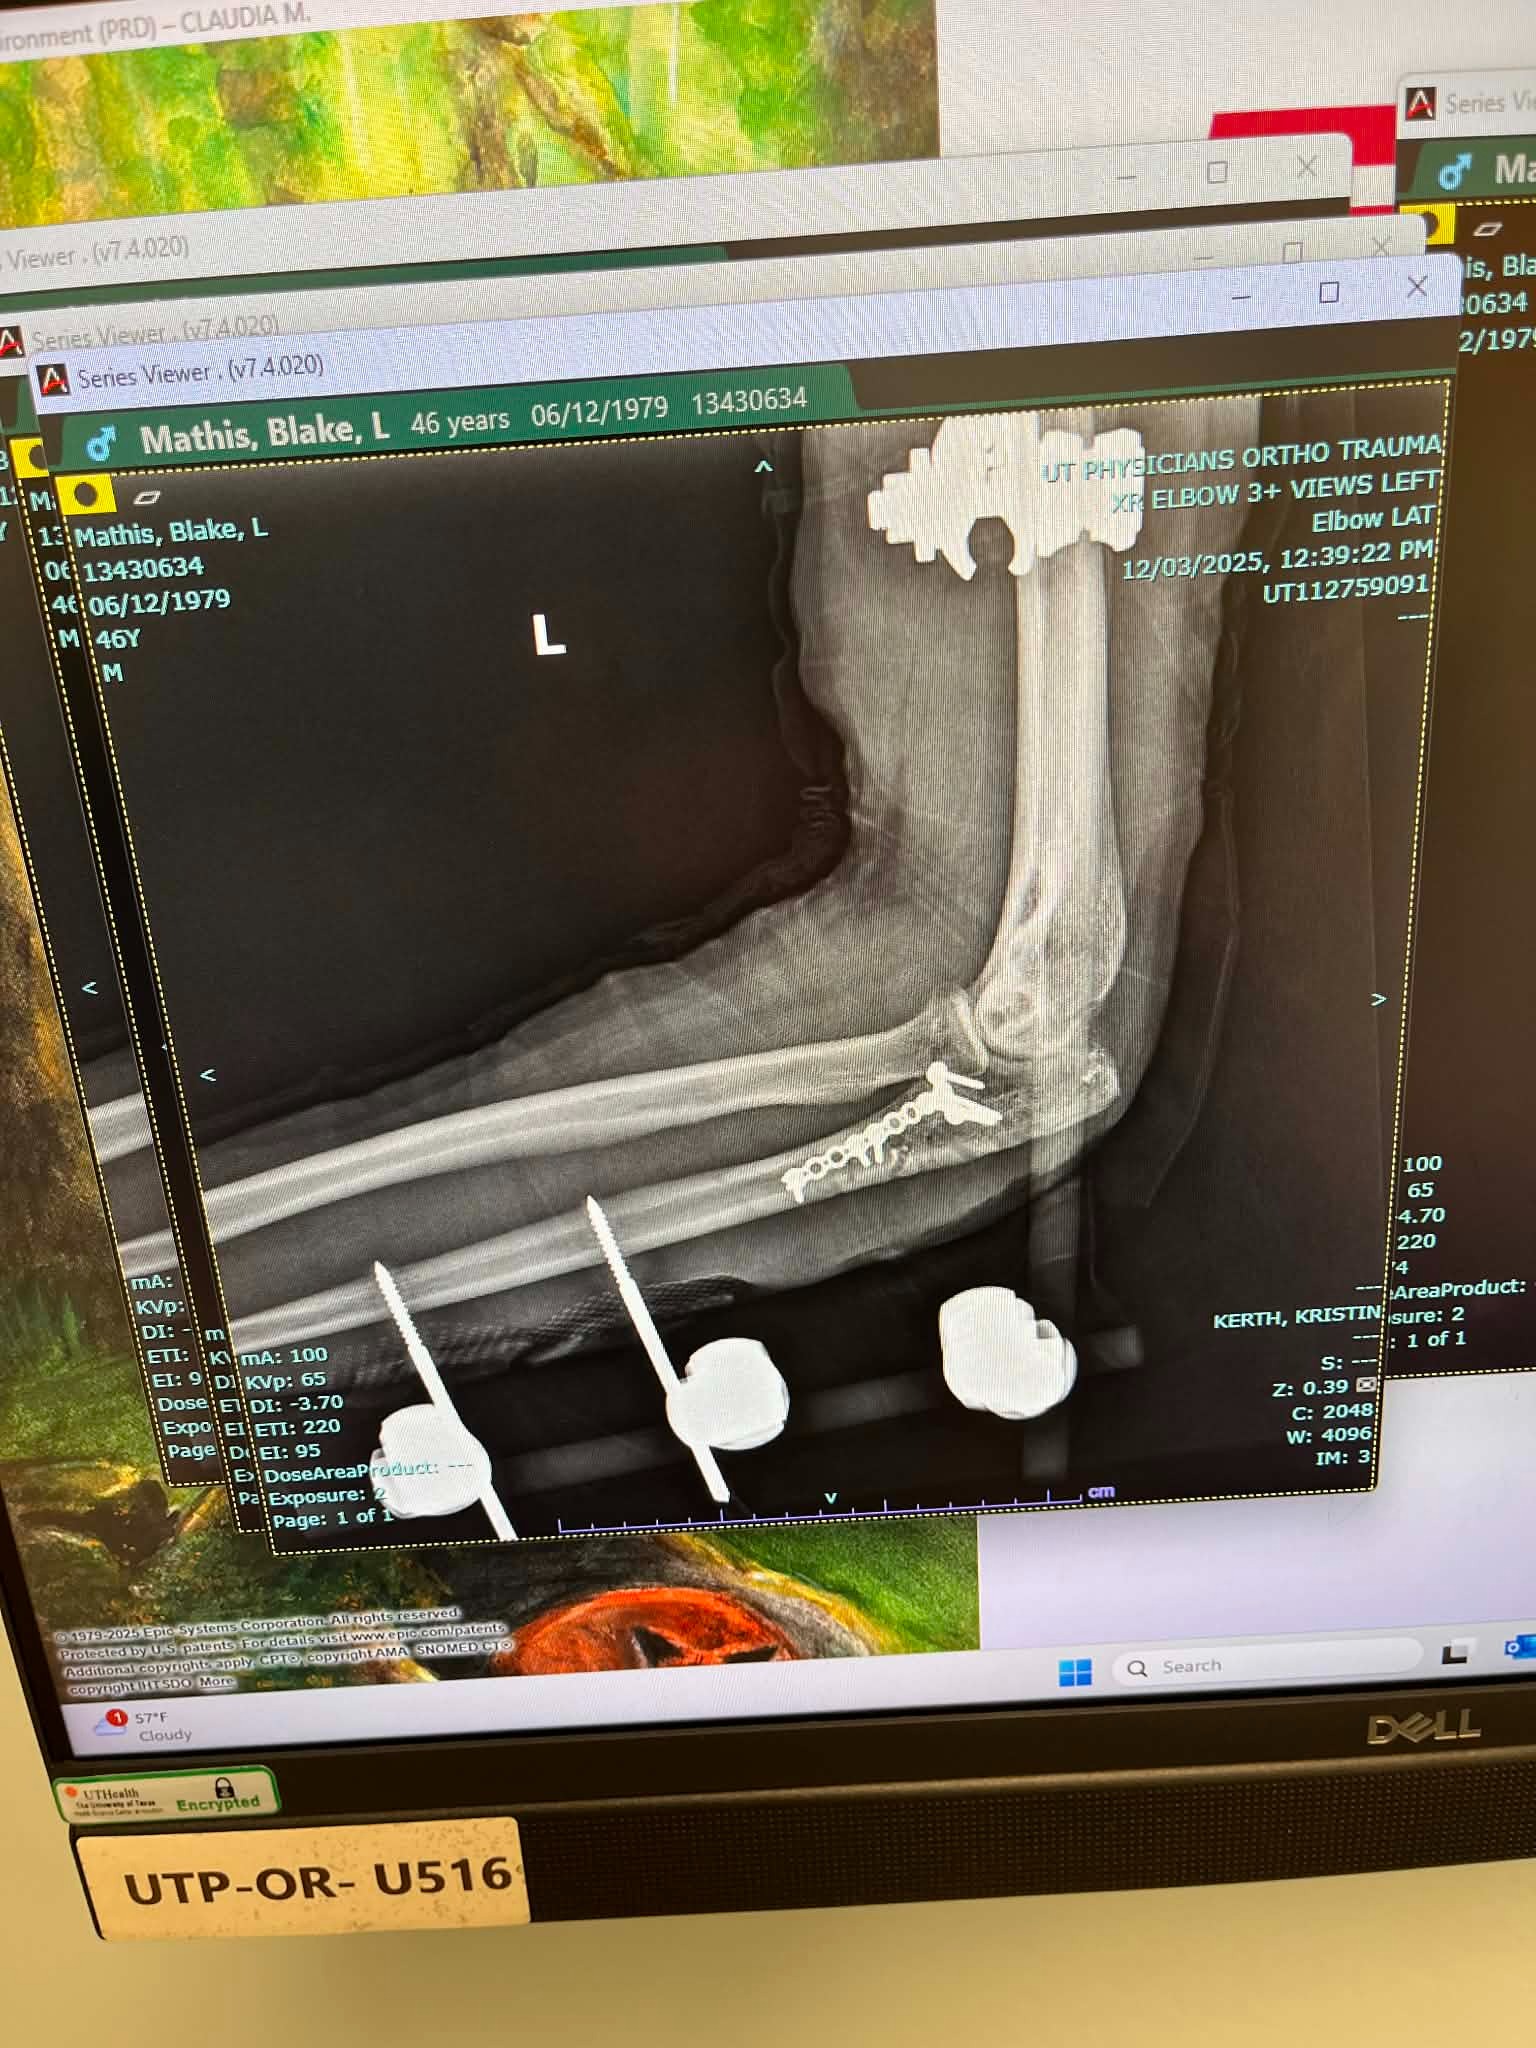

Since the accident, Blake has undergone four surgeries and is still in the long process of recovery. After the second surgery, he developed a staph infection when some of the hardware in his elbow poked through his skin. He spent five days in the hospital, had a PICC line and portable IV for a month, and had a nurse visit daily to administer medications and clean his wounds. His fourth surgery involved removing most of the hardware, as the staph infection was clinging to the metal. Now, Blake has two metal rods on the outside of his arm held in place by six screws, and his road to recovery is far from over. On top of the physical pain and uncertainty, Blake has been unable to work for six months, which has made it even more difficult to cover mounting medical bills and everyday expenses.